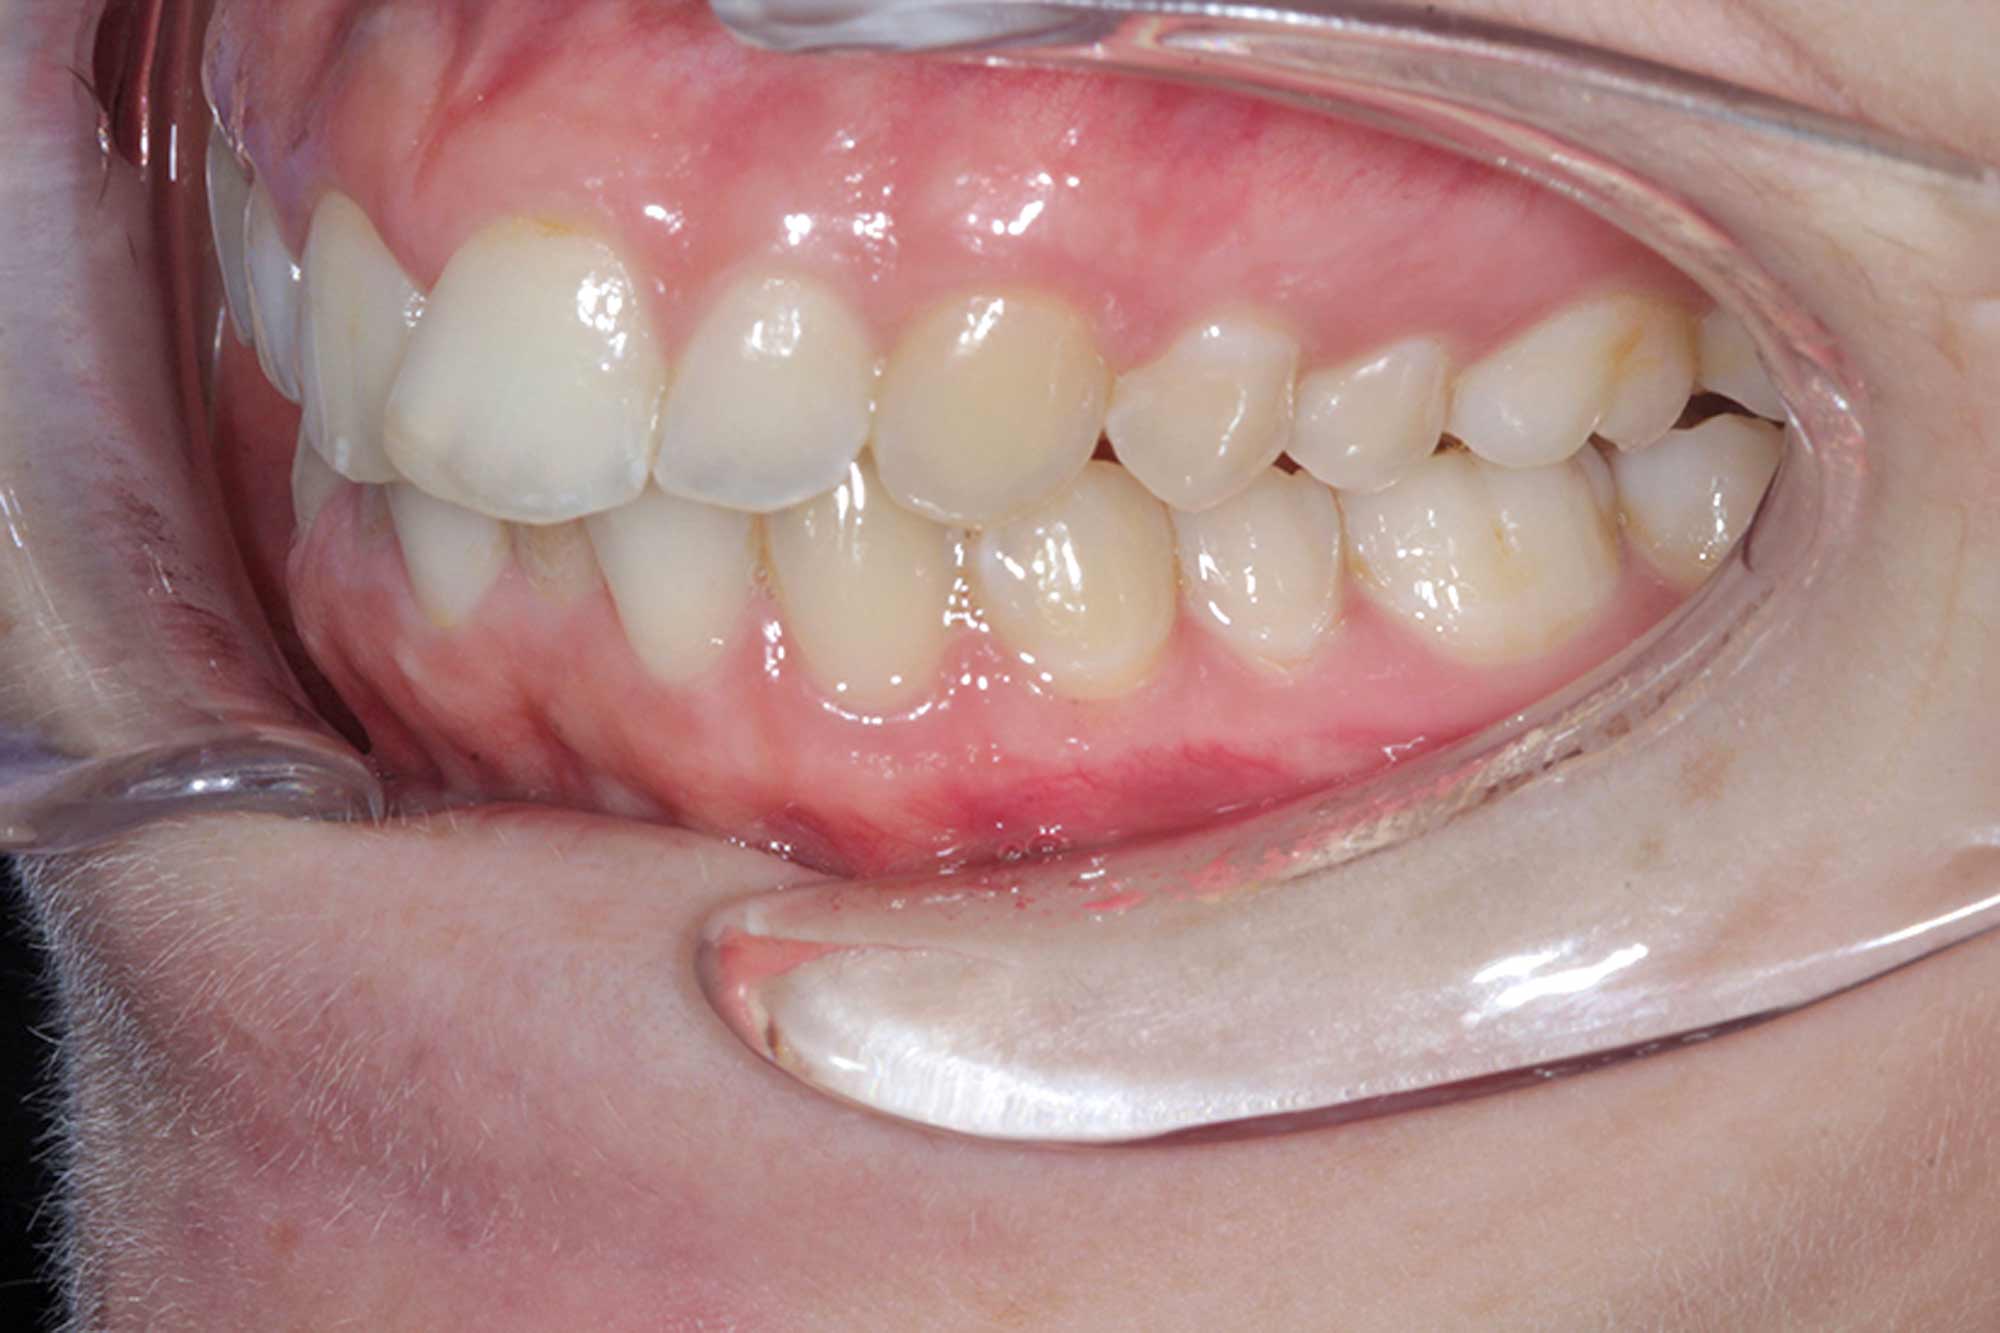

This young female patient presented with misalignment. She wanted a solution that would not only straighten her teeth but also give her the confidence in her smile she’d always wanted.

We started off with her aesthetic smile design, as we always do. She had beautiful smile proportions and the potential for perfection was certainly there as we concentrated on matching her gingival margins, widening her buccal corridors and accepting that incisal tooth wear had certainly taken place with some of the edges.

In this case, 14 aligners were needed to achieve the outcome we were looking for. This was followed by two short stages of refinements, as we certainly aimed for perfection in the end result and strived to match the original Clincheck prediction.